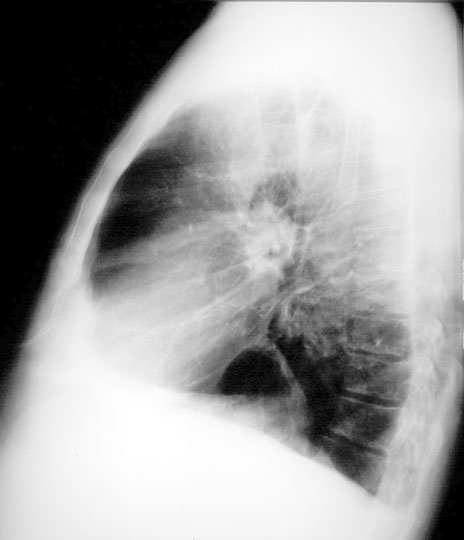

Case 35

Lateral

Close up

Labeled Image Most common cause for thin walled cavities?

You should probably ask which region?